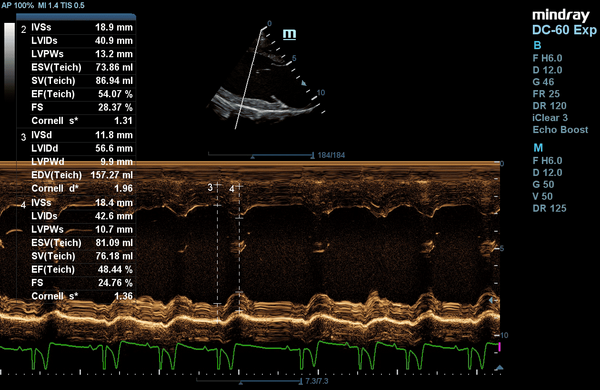

Anton, ein 4 jähriger Dobermann Rüde, wurde uns zur Kontrolle eines wurzelkanalbehandelten Zahnes vorgestellt. Da hierfür eine Narkose erforderlich war, führten wir vorher eine Herzabklärung durch.

Eine Röntgenuntersuchung verlief unauffällig. Bei der Ultraschalluntersuchung des Herzens (Echokardiographie) zeigten sich leider Veränderungen einer dilatativen Kardiomyopathie - DCM.

Hierbei handelt es sich um eine Erkrankung des Herzmuskels, welche mit einer verminderten Pumpleistung und einer Vergrößerung des Herzens einhergeht. Beim Dobermann ist diese Erkrankung genetisch bedingt. Andere betroffene Rassen sind beispielsweise Doggen, Neufundländer, Bernhardiner und irische Wolfshunde. Auch durch eine Mangelernährung mit Taurin oder Carnitin kann die Erkrankung entstehen.

Etwa jeder zweite Dobermann ist von der Erkrankung betroffen und jeder Dritte davon stirbt an einem plötzlichen Herztod, wenn die Erkrankung zu spät erkannt wird.

Er bekommt nun ein Herzmedikament, welches die Schlagkraft des Herzens verbessert und deutlich seineÜberlebenszeit trotz seiner Herzerkrankung verlängert und er wird in sechs Monaten zur Herzkontrolle vorgestellt.